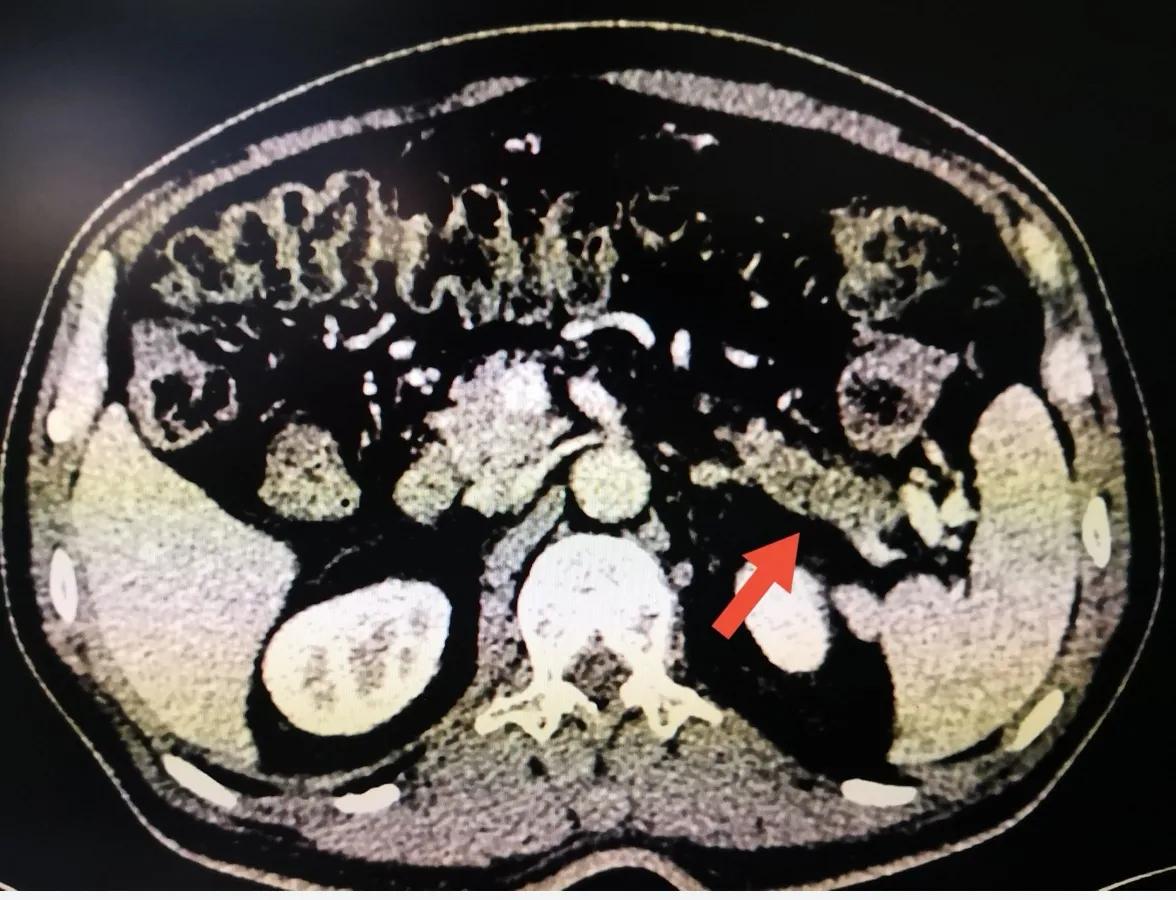

患者入院后行进一步检查,化疗检查肿瘤标记物CA-199 3500U/ml;腹部增强CT提示胰尾部囊实性占位,考虑恶性可能性大,未见明显肿大淋巴结;胃肠镜检查及心电图未见明显异常。

腹部增强CT见胰尾囊实性占位,箭头所示

增强CT下胰尾肿瘤